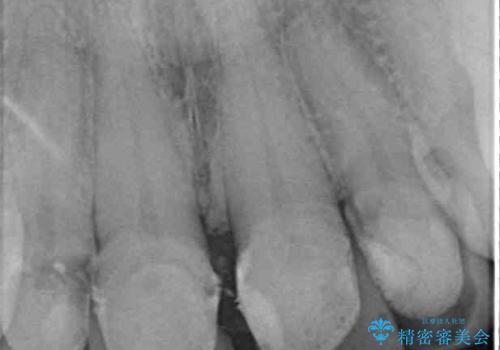

- 自宅近くの歯科医院にて前歯の詰め物が外れたことを機会に、オールセラミッククラウンへの変更を決断して4歯を仮歯に替えたものの、あまりに汚くて恥ずかしいとのことで来院された患者様です。

歯の形成量は不十分で形態は不自然、境目は不適で歯肉が腫れていたため、新しい仮歯に替えた後に歯肉の腫れが引くのを待ち、オールセラミッククラウンにて補綴することとしました。